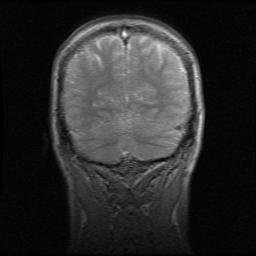

giraffe-leg-CT

This blog’s first image and subject: giraffe legs and modelling.

DSC_0203 Mystery Dissection 3  DSC_0963a  Whole 2 Gratuitious Melanosuchus (black caiman) shot. chicken-viscera-myopathy Gratuitious rhinoceros leg.  Kitty Hedz it is defunct rhino_front  hippo_L_knee Wolpertingers Jenny Hanniver- "face" windfall-croc (4) The nuchal ligament, which runs along the spine and helps hold up that long neck.  The left cheek's teeth-- and check out the spines on the inside of the cheek! Keratinous growths to aid in chewing, food movement, digestion etc. These extend into the stomach, too! Amazed me first time I saw them, in an okapi (giraffe cousin). my-brain2 If this post bummed you out, just focus on these contented cats. An offering to The Master

Personally, my post about my brain means a lot to me (and any zombies out there) of course, but also I’m rather keen on my entry on elephant biomechanical models (cheeseburger units!), and the posts about elephant foot pathologies and the rhino crisis also carried a strong, semi-personal urgency.

Here are some NEW images to ponder. One is… unpleasant; one is more abstractly technical; but both are about the bewitching power of anatomy. The coming year will run the gamut between these extremes:

PURPLE EMU WHOLE 1 _Se1_Im002